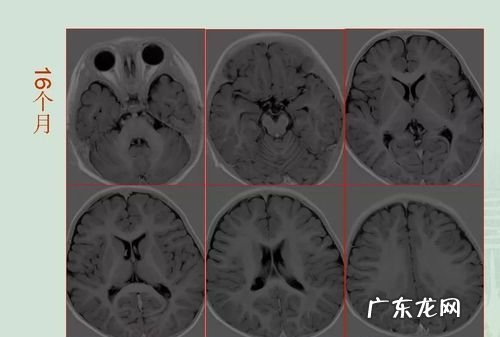

磁共振片子出了,报告没出可以看医生吗最上面一排英文从左到右是仪器的牌子和医院的名字好像是什么镇安中医医院 。

左上是图片的编号和体位第几系列第几张图是什么切面 。

右上是病人名字,医院编码,出生日期年龄性别,哪一天几点做的这个磁共振 。

下面的都是磁共振的技术参数 。